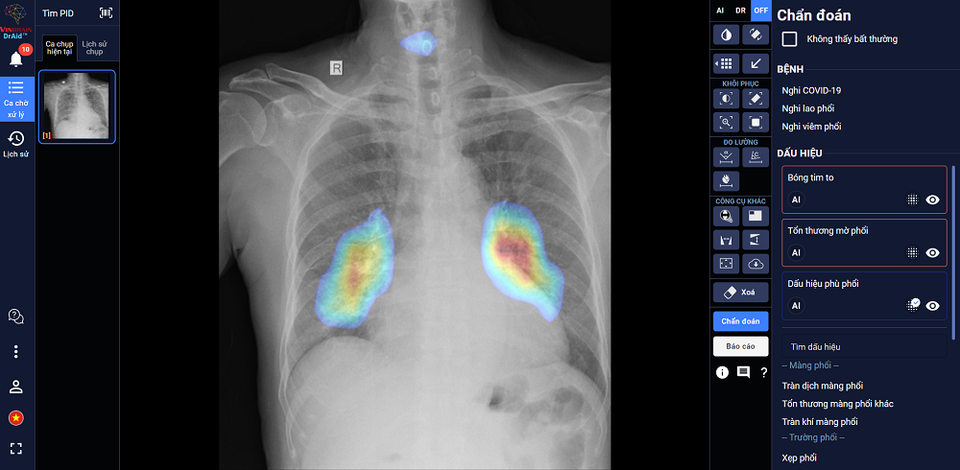

Giao diện của ứng dụng DrAid - AI trợ lý bác sĩ đầu tiên tại Việt Nam

Tháng 6/2020, các chuyên gia, nhà khoa học của VinBrain đã nghiên cứu thành công và ra mắt DrAid - AI trợ lý bác sĩ đầu tiên tại Việt Nam hỗ trợ chẩn đoán các dấu hiệu bất thường và bệnh lý về tim - phổi - xương dựa trên hình ảnh X-quang, trở thành công ty công nghệ đầu tiên ở Việt Nam ra mắt một sản phẩm AI cho y tế hoàn chỉnh.

DrAid được đào tạo dựa trên bộ dữ liệu lớn 1,3 triệu hình ảnh X-quang, trong đó hơn 326 nghìn hình ảnh được gán nhãn và bộ dữ liệu Covid-19 lớn thứ 2 toàn cầu với 7.592 hình ảnh dương tính của bệnh nhân Covid-19. Hiện DrAid có khả năng hỗ trợ chẩn đoán 20 dấu hiệu bất thường và bệnh lý về tim - phổi - xương dựa trên hình ảnh X-quang ngực với độ chính xác trên 88% trong vòng 5 giây, đồng thời tự động đưa ra báo cáo y tế theo chuẩn quốc tế JCI có khoanh vùng và đo kích thước chính xác tại khu vực bất thường.